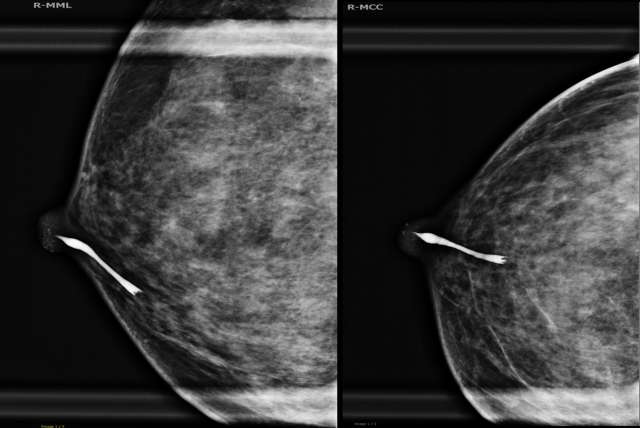

42-year-old female with a history of spontaneous, clear right nipple discharge.

Procedure Ductography Figure 1

Figure 1. Example of a ductogram image showing contrast filling the ductal system with an intraductal lesion visible as a filling defect. The discharging duct in the central region of the nipple was cannulated with a right angled tip cannula and 0.15 cc of water soluble Conray contrast was injected. Magnified CC and ML views of the right subareolar region demonstrates opacification of the ductal system at 6 o'clock. There is mild dilatation of the immediate subareolar duct and sinus with abrupt termination of the duct approximately 18 mm deep to the nipple related to a small intraductal filling defect. The ducts beyond this filling defect are not opacified.